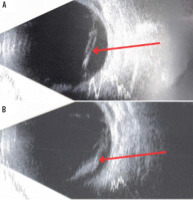

Figure 1

Fundoscopic examination of the left eye on the day of admission. Vitreous hemorrhage, a scleral wound at 10 o’clock surrounded by small hemorrhages, local retinal detachment, and hemorrhagic opacities in the nasal quadrants, hindering the assessment of the retina. A) Superior and inferior nasal quadrants of the left eye. Hemorrhagic opacities in the nasal quadrants. B) Superior and inferior temporal quadrants of the left eye